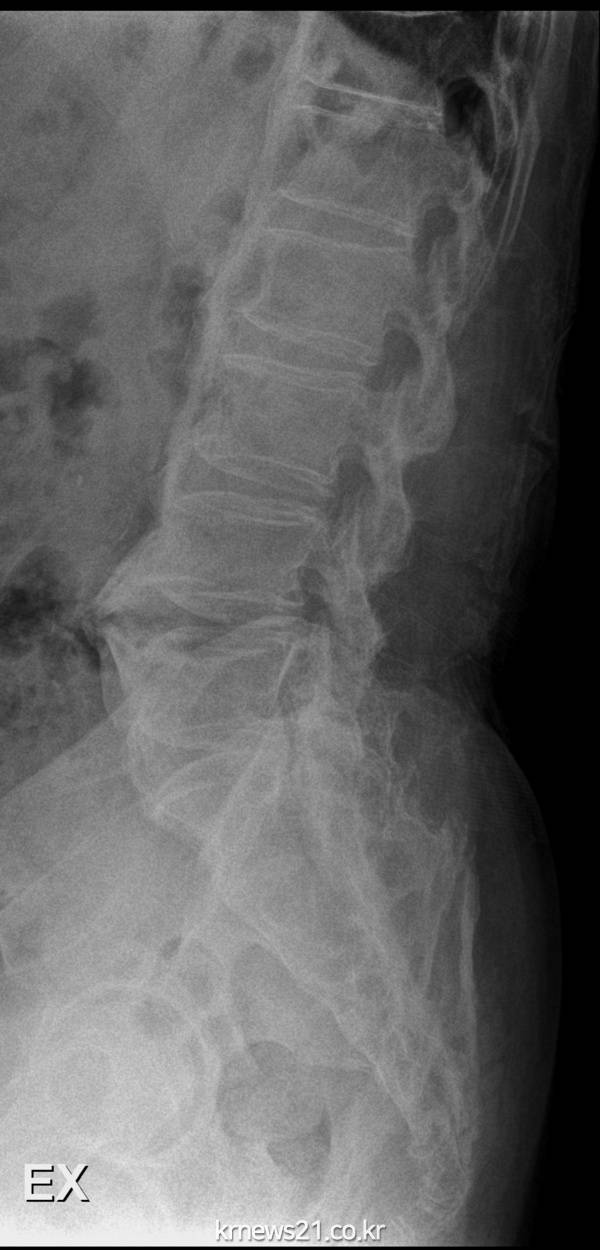

강직성척추염은 척추에 염증이 생겨 점점 허리가 굳는 병이다. 특별한 외상없이 기상 후 3시간 이상 허리 뻣뻣함이나 골반 통증이 있고, 3개월 이상 증세가 지속된다면 의심해볼 수 있다. 척추와 엉덩이 관절뿐 아니라 무릎 관절이 붓거나 발꿈치, 갈비뼈에 통증을 느끼기도 한다. 원인이 명확하게 밝혀지지 않았으나 HLA-B27이라는 유전자와 연관 있는 것으로 알려졌으며, 면역력 저하나 세균 감염 등의 다양한 요인이 영향을 미치는 것으로 보고된다.

강북 힘찬병원 백경일 병원장(신경외과전문의)은 “강직성척추염초기에는 통증만 오지만 빨리 치료하지 않으면 척추 뼈 사이의 인대가 굳어 허리를 굽힐 수 없을 정도로 뻣뻣하게 굳을 수도 있다”며 “젊은 남성 중 이유 없는 허리와 골반 통증이 일정 기간 지속되는 경우, 가족 중 이 질환을 앓고 있는 경우에는 가벼운 증상이라도 병원을 찾는 것을 권한다,”고 말했다.